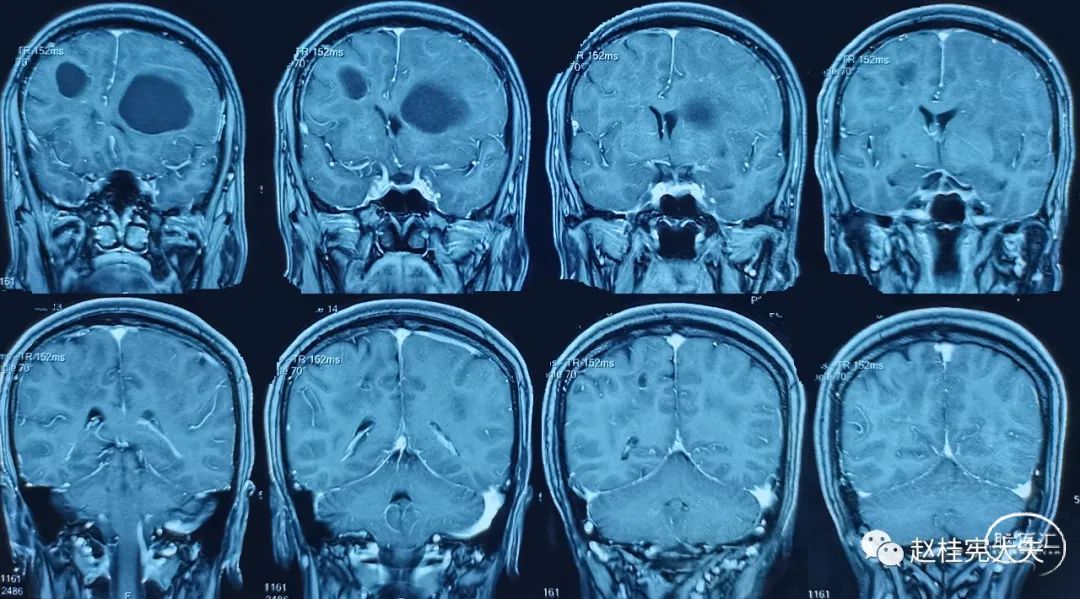

专病门诊时间,家属带患者来就诊。病史很简单,女性患者,56岁,以“反复头痛8年,加重2月”就诊。患者于8年前因头痛查颅脑CT提示颅内多发低密度影,行颅脑磁共振平扫+增强提示颅内多发病变,多个小囊,脑白质病变,病灶部分不规则强化,当地医院以寄生虫病服用打虫药3个疗程,症状同前,复查颅脑磁共振病灶未见明显变化。后未进一步诊治。2021年9月,因头痛加重,再次复查头颅磁共振平扫+增强提示颅内多发较大囊肿,弥漫性脑白质病变,再次查寄生虫抗体均阴性。目前诊断不明。